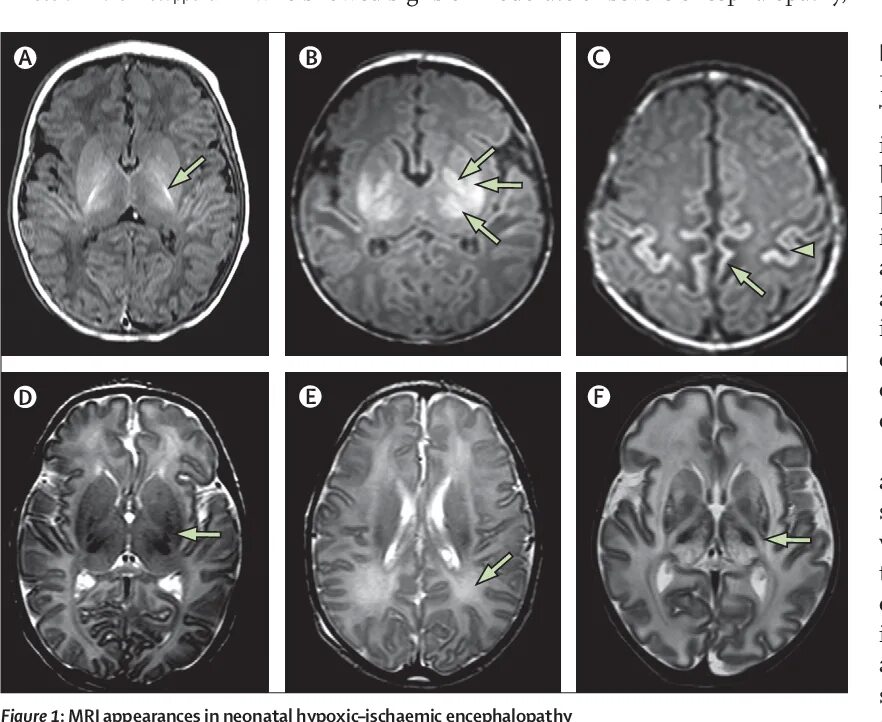

Кровоизлияние в мозг у новорожденного степени